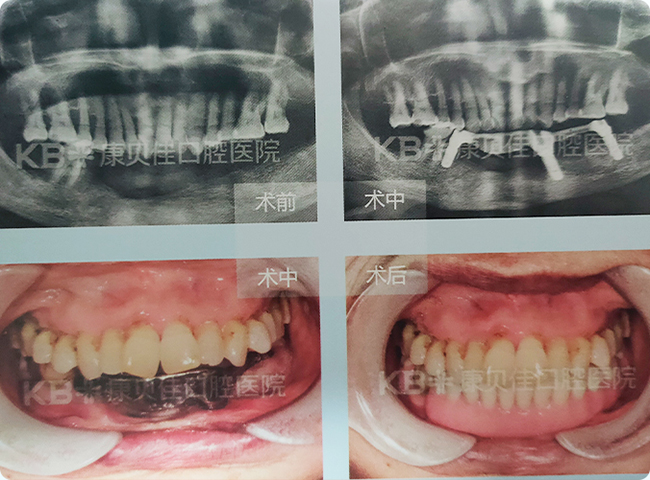

梅女士 64岁

下牙几乎全部缺失,仅剩一颗,牙槽骨条件不符合常规种植,多方求医无果。在妹妹的介绍下来到康贝佳,检查发现其牙槽骨吸收严重。康贝佳口腔种植专家为其定制了种植杆卡修复,帮助其重拾好口福。

治疗方案:

杆卡 下颌 种植3颗